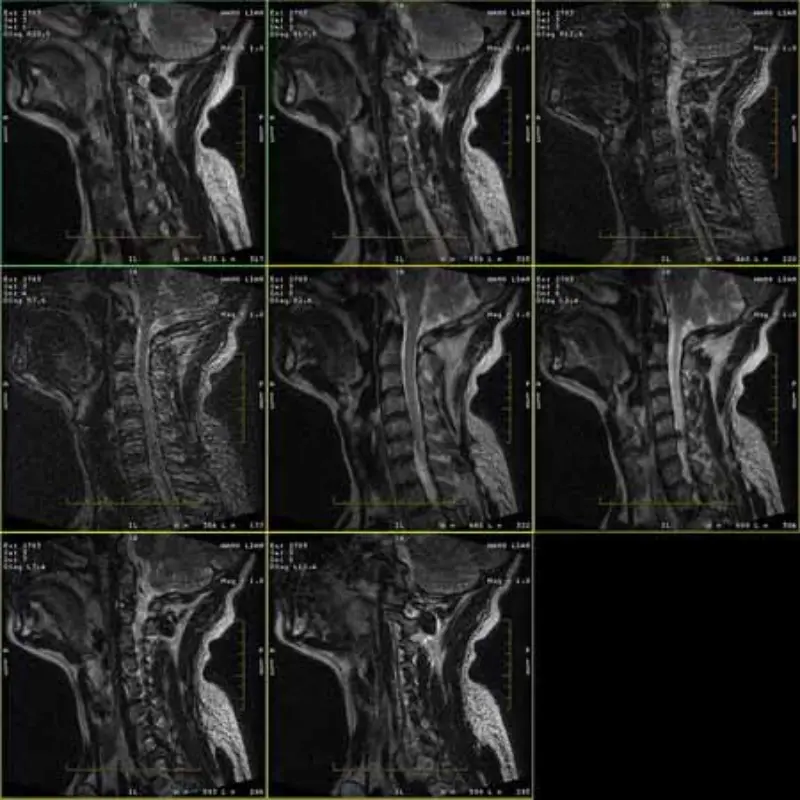

FRFSE နှင့် GRE ပရိုတိုကောများ၏ ပုံများတွင် သရဲများပါရှိပြီး တစ်ခါတစ်ရံတွင် စီးရီးတစ်ခုတွင် SNR နိမ့်သောပုံများ ပေါ်လာသည်။ ဒါပေမယ့် SE protocol ပုံတွေက ပုံမှန်ပါပဲ။

ပူးတွဲပါပုံများကိုကြည့်ရှုပါ။